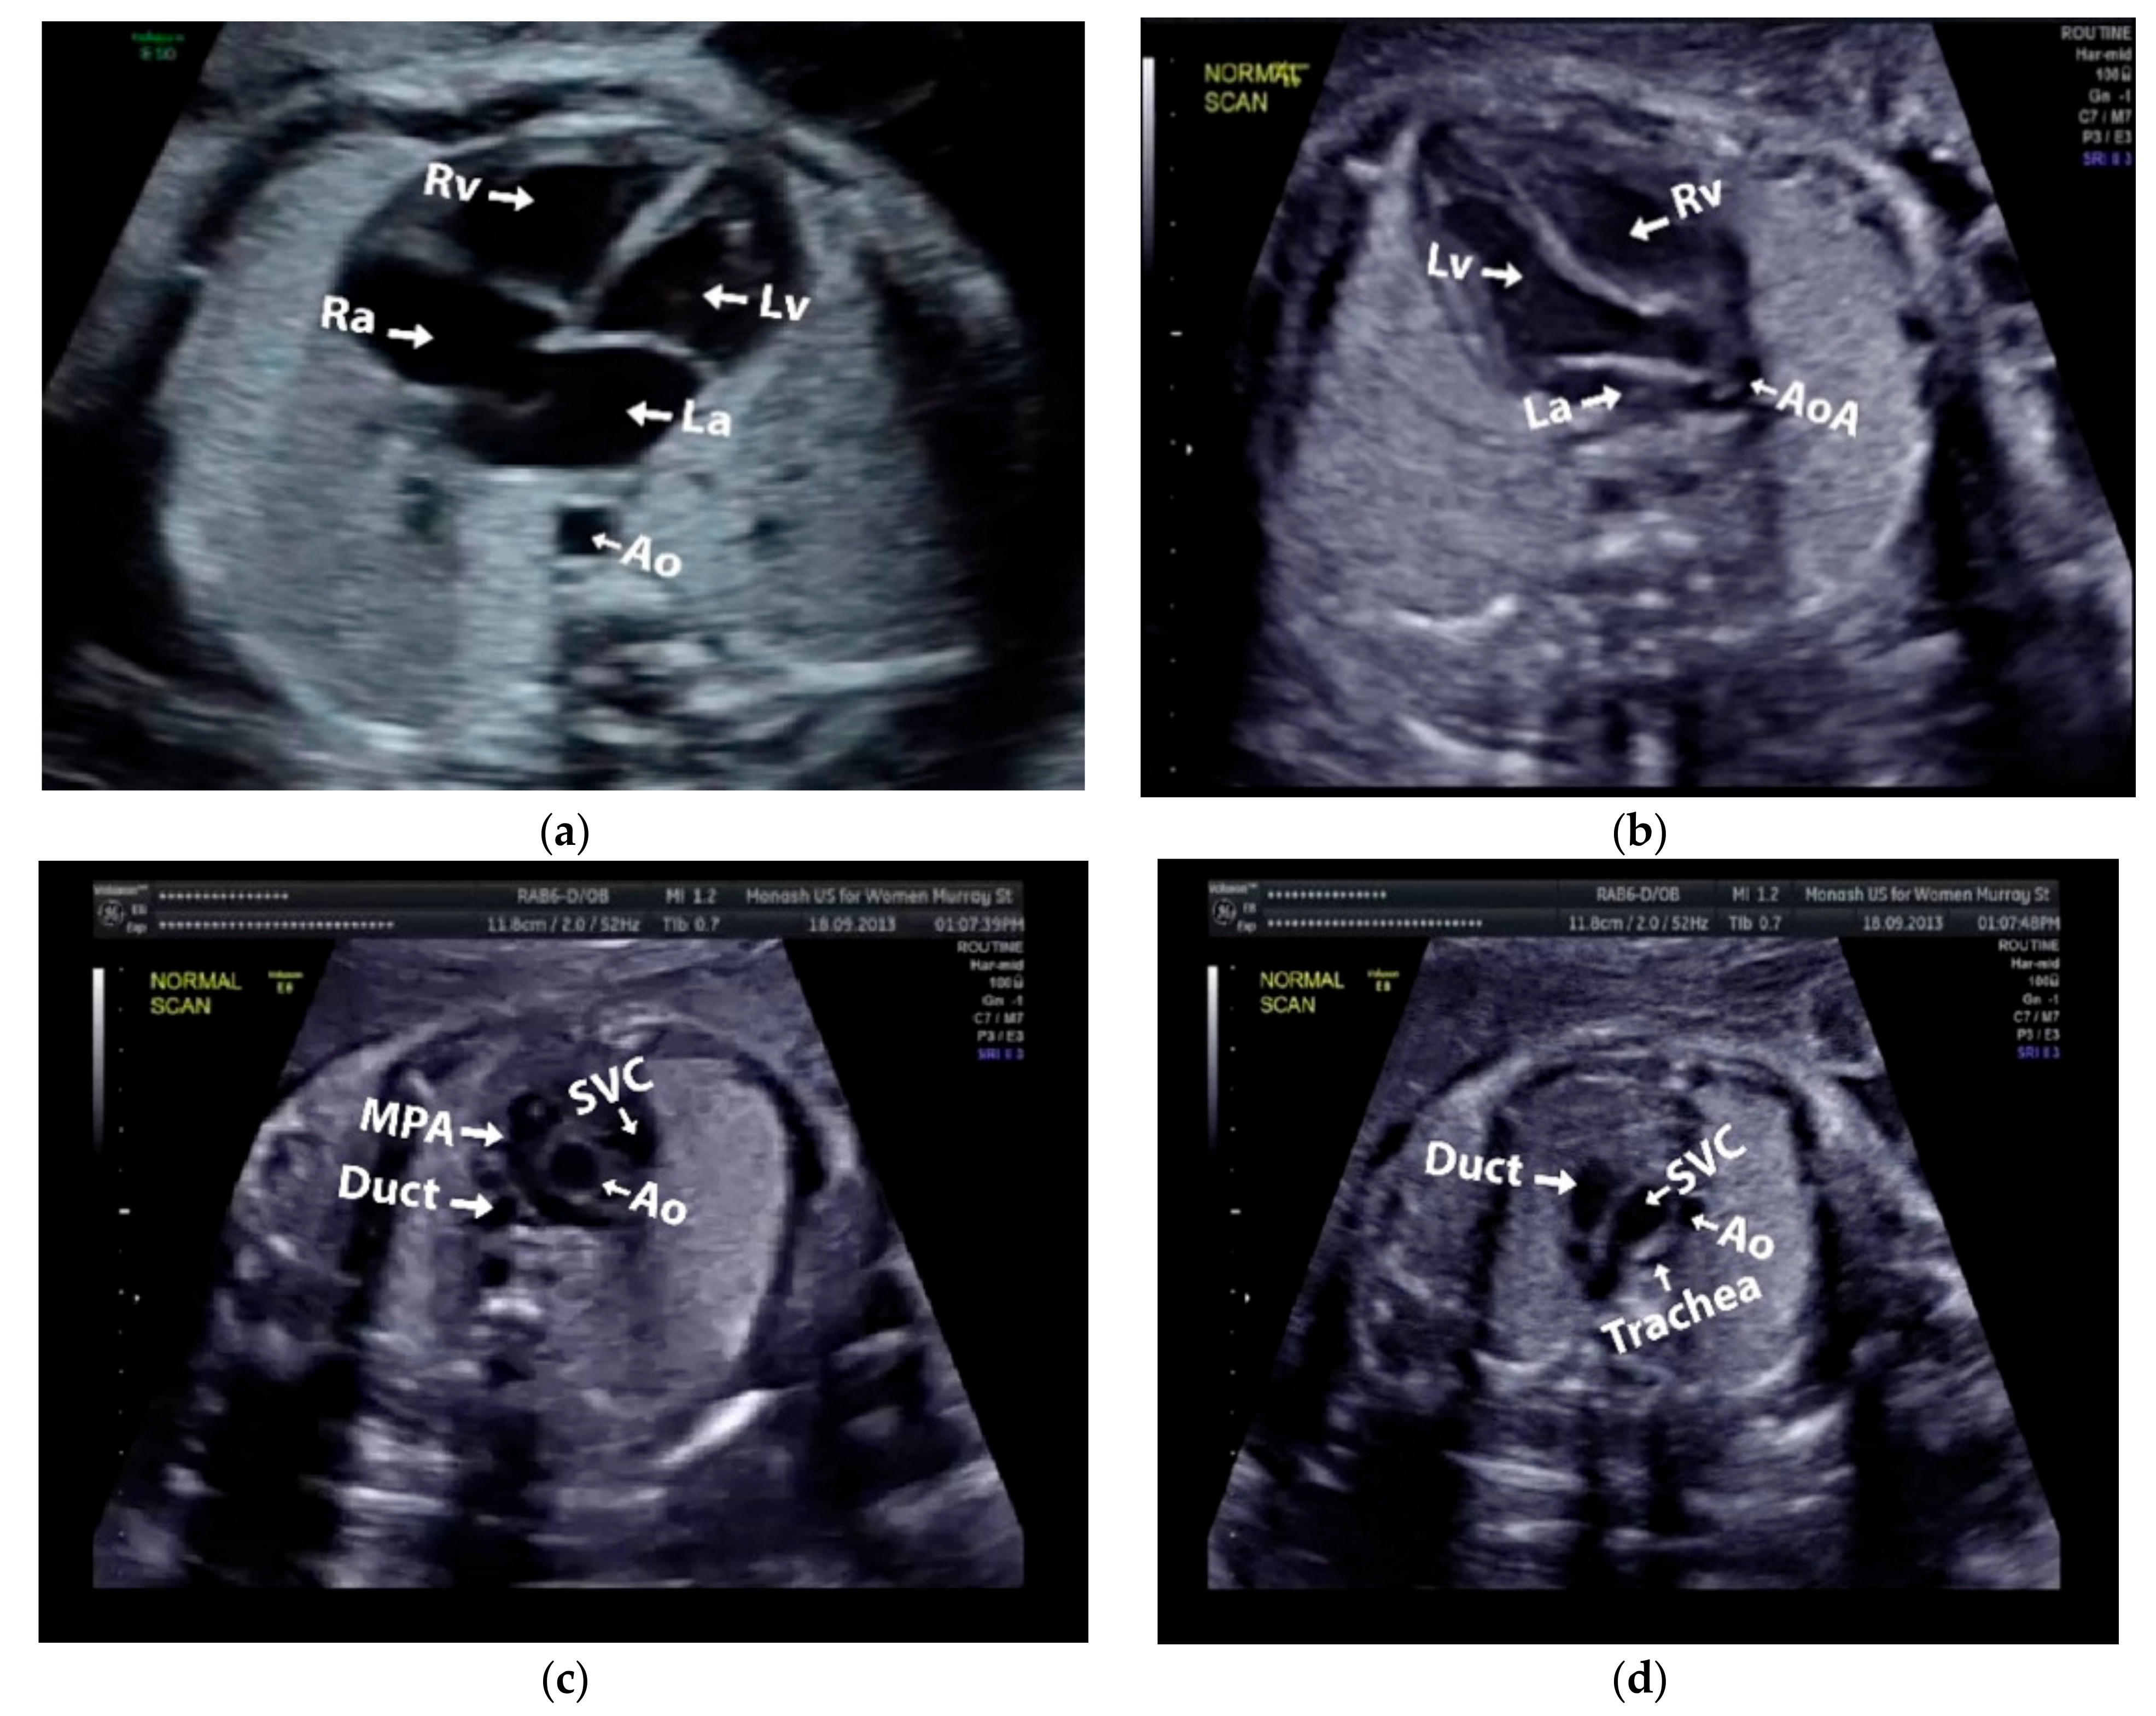

Images with inappropriate anatomical planes (cropped or badly captured) and those with calipers were excluded. The dataset composition was clearly imbalanced (some classes were more frequent than others), as is usually the case in real clinical scenarios. The sample of the raw ultrasound image was based on four views in normal anatomy, as depicted in Figure 2. In such sample, there are the left atrium (LA), left ventricle (LV), right atrium (RA), right ventricle (RV), ductus arteriosus (DUCT), superior vena cava (SVC), aorta ascendens (AoA), aorta descendens (Ao), and main pulmonary artery (MPA), whereas the sample of the raw ultrasound image of abnormal anatomy structure, with the three heart defects such as ASD, VSD, and AVSD condition, is compared to normal anatomy structure in Figure 3. In the abnormal structure, there are hole (H) as heart defect in each condition. Each defect has the variation of hole size; such hole size indicates the disease severity. However, in this study, we only detected the hole, without measuring the hole size.

Figure 2.

Fetal heart scan in four standard views of normal anatomy: (a) 4CH; (b) LVOT; (c) RVOT; and (d) 3VT.